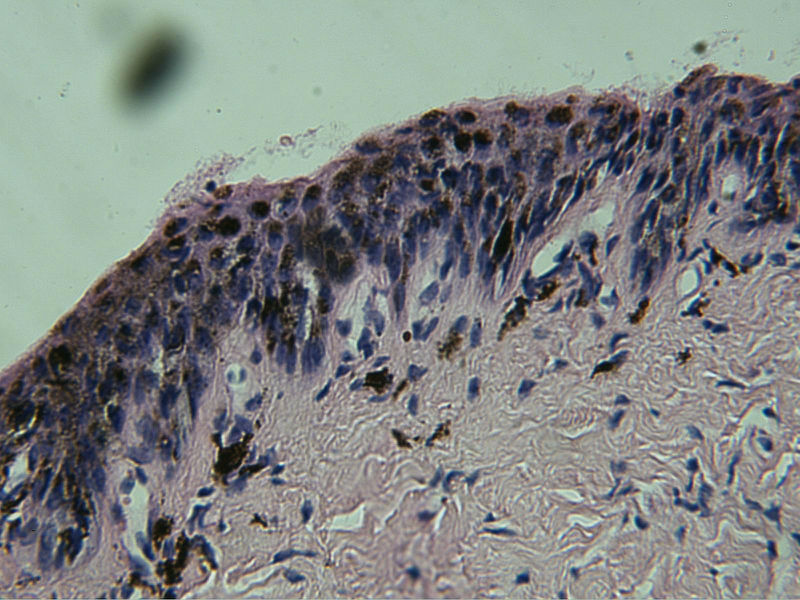

病理二:甲母痣?黑素瘤?

患者女,25岁,左无名指甲变黑1年余

考虑原位肢端黑素瘤

考虑甲下原位黑素瘤。

需要考虑原位恶黑,无论临床和病理都支持!

临床皮损在甲根已见黑色斑,病理改变基底层黑素细胞增生活跃。要考虑原位肢端黑素瘤了。